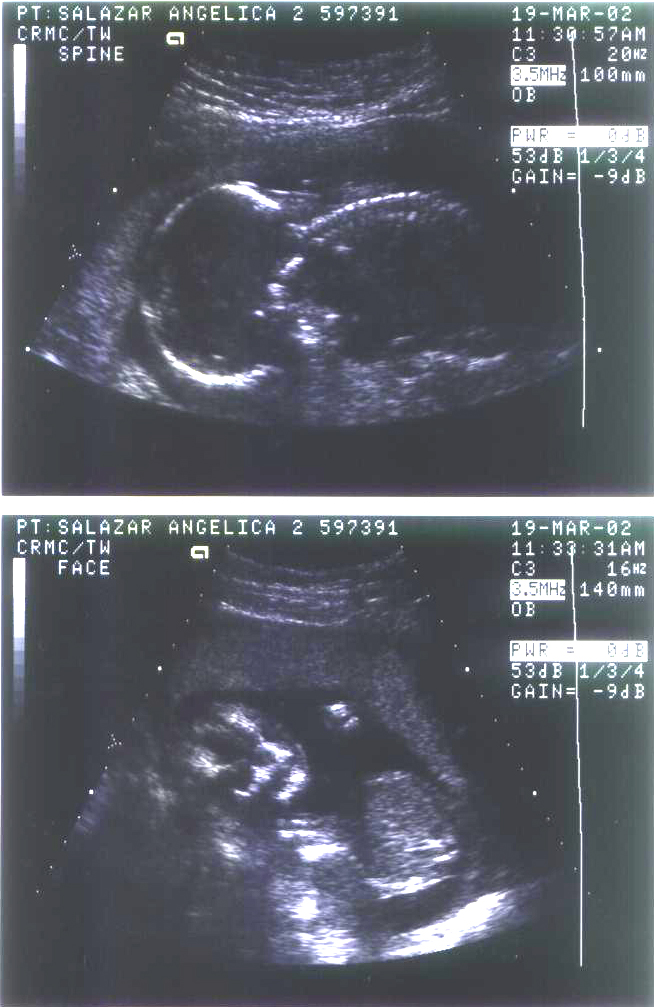

Aqui van

mis primeras fotitos... que

las disfruten...

13

Semanas |

17